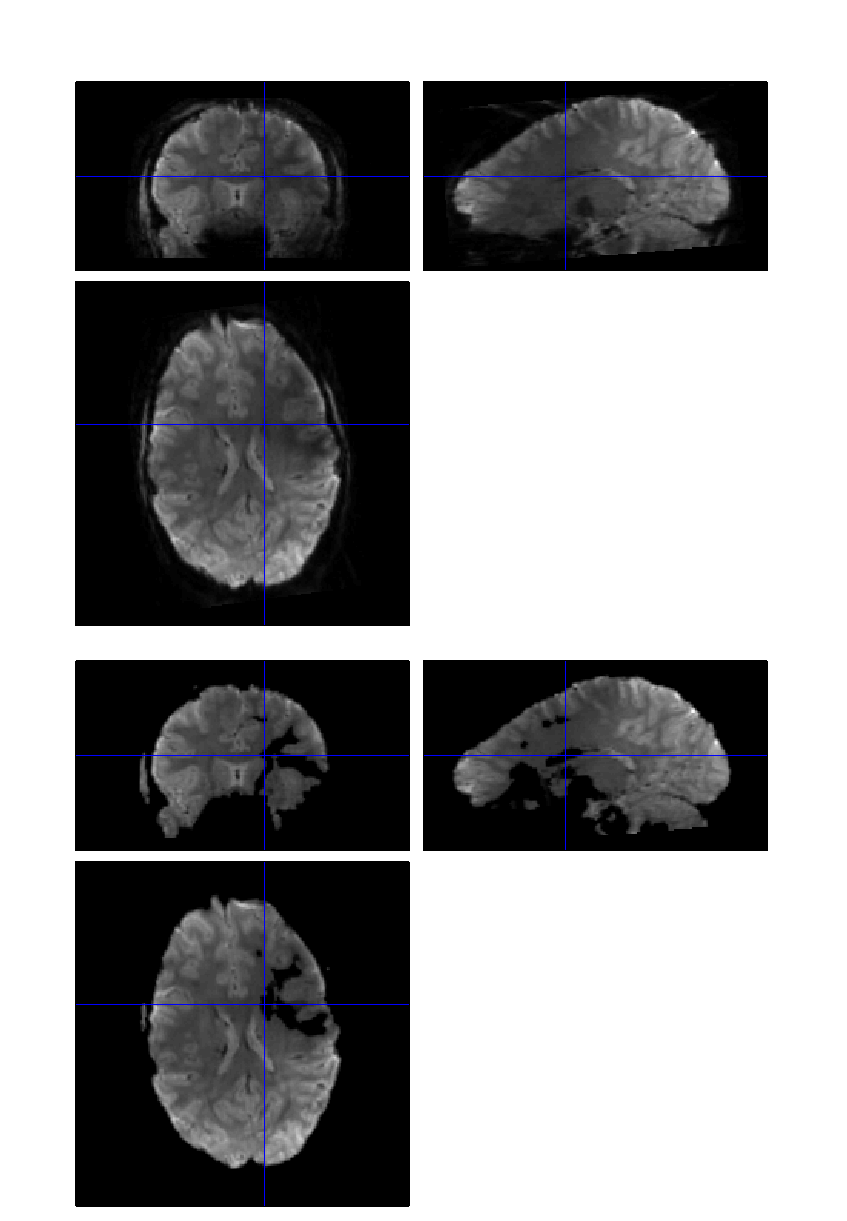

I got this weird result of despiking running the BIDS pipeline BIDS 7t_trt. Some part of the EPIs have been zeroed when visual inspection told me they were fine.

With my experience with 7T data I suspect that some of the stuff designed for 3T might not behave well on 7T data but I might have overlooked something else. Any idea?

Above: before despiking

Below: before despiking